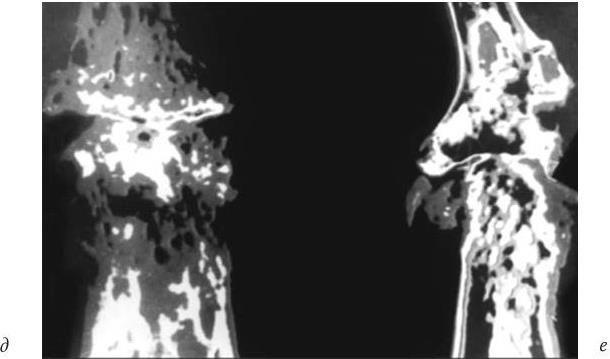

а, в — прямая проекция; б, г — боковая проекция. Пояснения в тексте Рентгенограмма дистального межфалангового сустава III пальца больного IV стадией первичного остеоартроза (5-кратное увеличение рентгеновского изображения) (окончание):

д — прямая проекция; е — боковая проекция

Обработка изображения на ЭВМ методом амплитудного рельефа: четко представлена деформация костных балок (новообразованная костная ткань накладывается холмами на поверхность кости), толстый слой неравномерного субхондрального склероза, мелкие кисты с костной стенкой, не обнаруженные даже при прямом многократном увеличении, и видоизмененная полость сустава (см. рис. 10, в); значительная деструкция костных балок эпифизов, склероз подхрящевых отделов, слоистая структура остеофита и трансформированная полость сустава (см. рис. 10, г).

Обработка изображения на ЭВМ методом эквиденситных полей: видно грубое преобразование всей трабекулярной структуры, в зонах перестройки теряется трабекулярность (неодинаковой формы и размеров очаги костной плотности), костная ткань распределена по всей ширине кости, отмечается резкое изменение трабекулярной структуры и деформация зоны ядра эпифиза, отсутствует плотная часть, соответствующая костномозговому каналу (см. рис. 10, д, е). Используя магнитно-резонансный томограф, можно определить толщину, объем, геометрию и топографию поверхности хряща, выявить кистовидные изменения в субхондральной зоне. Но обнаружена лишь частичная конкордантность повреждений хряща при МРТ (Коваленко В. Н., 2003). Автор отмечает возможность точного измерения толщины суставного хряща при использовании высокочастотного УЗИ, но показывает, что наиболее достоверное измерение толщины хряща и суставных тканей дает артроскопия.